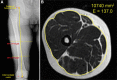

Background: High tibial osteotomy (HTO) is an effective surgical method for treating medial compartment osteoarthritis. However, in most cases after surgery, muscle strength is decreased, and rapid muscle atrophy is observed. Therefore, the purpose of this study is to verify the effects of low-intensity resistance exercise (LIE) with blood flow restriction (BFR) on the cross-sectional area (CSA) of thigh muscles, knee extensor strength, pain, and knee joint function and investigate proper arterial occlusion pressure (AOP) in middle-aged women who underwent HTO.

Method: This study was designed as a prospective randomized controlled trial. Forty-two middle-aged women who underwent HTO were randomly divided into three groups and participated in LIE with (40% or 80% AOP applied) or without BFR. The main outcome was the measurement of the CSA of thigh muscles (at 30% and 50% distal length of the femur) before and 12 weeks after treatment. Additionally, knee extension muscle strength, pain, and joint function were evaluated before and 6 and 12 weeks after treatment.

Results: CSA of thigh muscles at 30% and 50% distal length of the femur decreased in the AOP 40% and control groups and was the largest in the AOP 80% group 12 weeks after treatment. Knee extension strength increased in all groups and was the highest in the AOP 80% group 6 and 12 weeks after treatment. Pain improved in all groups, with no intergroup differences. Knee joint function improved in all groups and was superior in the 80% AOP group 12 weeks after treatment.